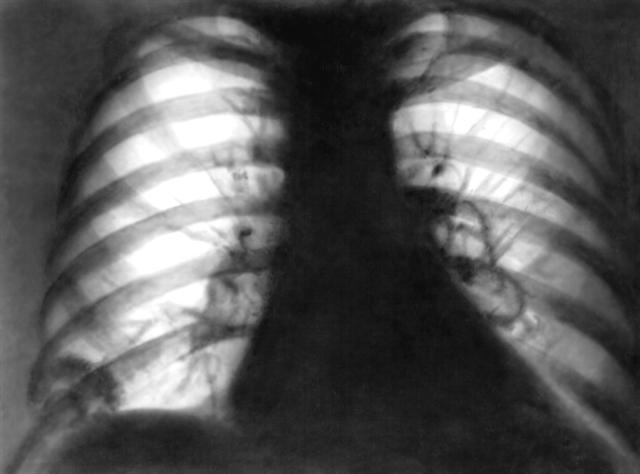

Рис. 2. Рентгенограмма легких: инфильтрат над диафрагмой справа, две полости распада в области левого корня.